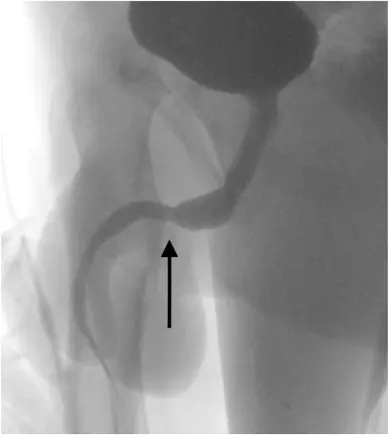

วันที่ 17 กันยายน 2564 สำนักข่าวต่างประเทศ รายงานว่า เด็กหนุ่มชาวอังกฤษวัย 15 ปี ที่ขี้สงสัยของเขาทำให้ต้องลำบากถึงคุณหมอ หลังจากที่เขาสอดสาย USB เข้าไปในอวัยวะเพศของตัวเอง เรื่องนี้ถูกเปิดเผยใน Urology Case Reports ซึ่งเป็นวารสารการแพทย์ โดยเด็กชายนำสาย USB เข้าไปในอวัยวะเพศ ซึ่งได้นำส่วนที่เป็นก้อนปมยัดเข้าไปทางรูอวัยวะเพศจนเกิดการอักเสบและฉี่เป็นเลือด

เนื่องจากสายเข้าไปติดอยู่ภายในท่อปัสสาวะ โดยมีส่วนหัว USB ทั้ง2 ฝั่ง ห้อยออกมาภายนอก ซึ่งเด็กหนุ่มได้พยายามจะดึงออกเองอยู่หลายครั้งแต่ก็ไม่สำเร็จ จนในที่สุดทางครอบครัวก็ช่วยกันนำตัวเขาส่งไปยังโรงพยาบาลท้องถิ่นแต่ ทางโรงพยาบาลไม่สามารถทำการรักษาได้เนื่องจากการกระทำดังกล่าวส่งผลทำให้เกิดภาวะโลหิตจาง จึงส่งตัวเด็กหนุ่ม ไปยัง University College Hospital London เพื่อทำการผ่าตัดด่วน